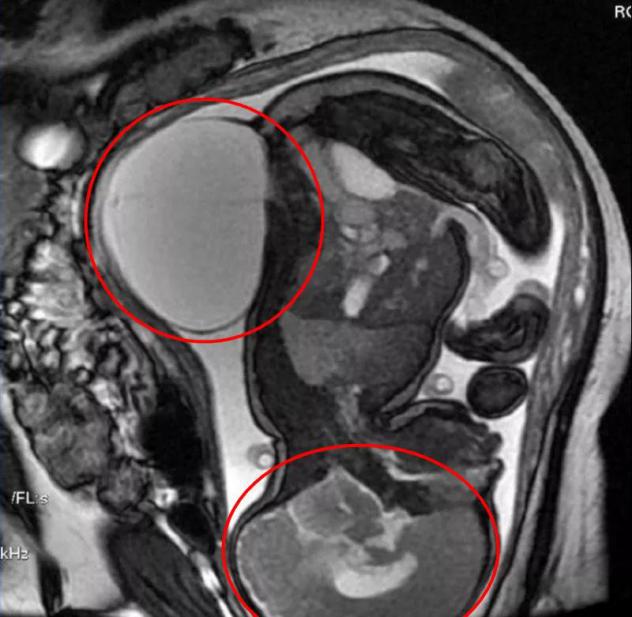

骶尾部畸胎瘤

据介绍,彩超由于其无创,廉价,快速等优势成为产检的首选,但是彩超有一些不足之处,比如视野小,而且在某些特殊的情况下存在显示欠佳的情况。由于磁共振对软组织(肌肉,脂肪,皮肤等等)的分辨率很高,不受胎儿骨骼和羊水量的影响,特别在羊水量较少或者胎头较大,或胎头已经入盆后,能很好的显示胎儿的全貌。磁共振是在不同的维度呈像,基本可以看清胎儿的各种角度,进行精确的测量。

脊膜膨出+脑积水

连体婴儿

那么,在什么情况下需要做磁共振?专家表示,磁共振可以应用于胎儿的各个系统诊断,中枢神经系统,颈胸腹部,盆腔等疾病的诊断,特别是胸部疾病诊断,中枢神经系统疾病诊断,和羊水过少的情况需要做磁共振。如果需要量化评价胎儿肺部发育不良的程度以及需要对脐带和胎盘的疾病进行诊断的情况下,磁共振检查也是很好的选择。在产妇过度肥胖,羊水过少,子宫肌瘤,多胎及胎儿复杂畸形时,磁共振比彩超有优势。同样的,磁共振可以是胎儿超声诊断的另一种补充。